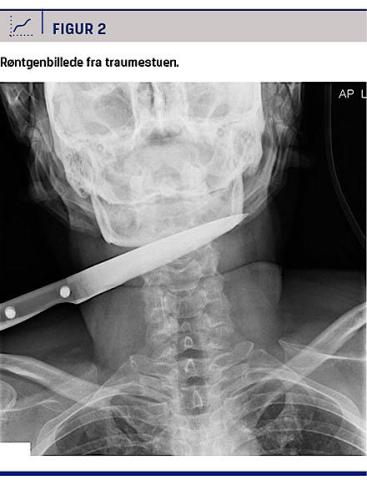

En 52-årig mand blev indbragt til et traumecenter med en halslæsion. I suicidalt øjemed havde han påført sig en stiklæsion i højre side af halsen med en grillkniv. Ved ankomsten til traumestuen sad kniven fortsat i halsen (Figur 1). Patienten var fikseret pga. risiko for yderligere selvmutilering. Han var under let sedering med propofol, men vågen og havde ikke behov for medikamenter eller maskeventilation. Alle vitalparametre var i normalområdet. En traumerøntgenoptagelse viste et knivsblad, der var 11 cm langt og gik på tværs gennem halsen. Akut UL-skanning af halsen foretaget af både vagthavende øre-næse-hals-læge og en radiologisk traumevagt var uden tegn på hæmatom. Forud for intubation og generel anæstesi blev de øvre luftveje vurderet og fundet i orden ved fiberlaryngoskopi. Der blev herefter foretaget CT-angiografi, hvor man heller ikke kunne påvise igangværende blødning. Man fandt, at kniven lå i det retrofaryngeale rum klos på columna cervicalis på C2-C3-niveau med spidsen i umiddelbar proksimitet af den kontralaterale a. carotis interna

(Figur 2). Patienten blev kørt til operationsstuen på øre-næse-hals-afdelingen, hvor kniven blev ekstraheret. Der var efterfølgende vedvarende, sivende blødning fra indstiksstedet, og man besluttede at eksplorere såret kirurgisk i samarbejde med en karkirurg. Herved blev der afsløret en vertikal læsion af vena jugularis interna, der måtte ligeres. Der blev i alt givet 3 × 300 ml SAG-M, 3 × 300 ml friskfrosset plasma og 1 × trombocytkoncentrat. Under anæstesien blev patienten øsofagoskoperet og trakeoskoperet. Der blev ikke fundet synlige læsioner af mucosa. Ved gennemgang de følgende dage var der ingen tegn på nerveskade ved objektiv undersøgelse. Patienten blev to dage postoperativt overført til en psykiatrisk afdeling uden men fra knivstikket, men i profylaktisk antibiotisk behandling. Der blev i efterforløbet ikke foretaget yderligere kirurgisk behandling.